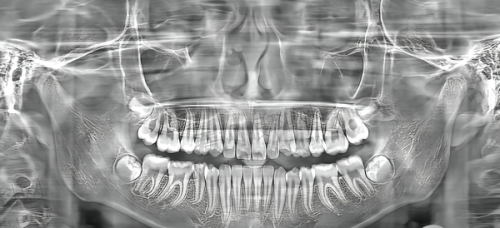

宁德蕉城牙院长口腔门诊部的诊疗项目丰富多样,常规项目涵盖了种植牙、牙齿矫正、牙齿美白、补牙、儿童牙科、牙周治疗、牙齿修复等多个方面。具体包括隐形矫正、金属自锁矫正、陶瓷自锁托槽矫正、即刻种植牙、微创种植、all - on - 4种植、全口半口种植、即刻拔牙即刻种植、个性化种植修复、美学种植修复、根管治疗、口腔麻醉、阻生智齿拔牙、牙贴面、美白牙齿、补牙、拔牙、洗牙、儿童龋齿、儿童补牙、儿童预成冠、儿童早期矫正预防等。

在种植牙技术方面,除穿颧穿翼种植牙外,其他牙齿缺失种植都能开展,如单颗缺失、多颗牙缺失、半口牙齿缺失、全口无牙颌种植等。门诊部采用3D微创种植牙技术、即拔即种、即刻负重、ALL - ON - 4半全口种植技术(4颗种植体就可以修复半口牙)等精良技术,这些技术能够减少患者的痛苦,缩短治疗时间,提高治疗成效。

牙齿矫正技术上,常采用数字化美学正畸,可通过3D数字化牙齿矫正技术获取牙齿的数据,让矫正牙套更符合顾客的牙齿情况。同时,门诊部拥有自锁托槽矫正、Insignia数字化美学矫正、时代天使隐形牙套、美国进口隐适美隐形牙齿矫正等特色矫正技术,为患者提供了更多的选择。